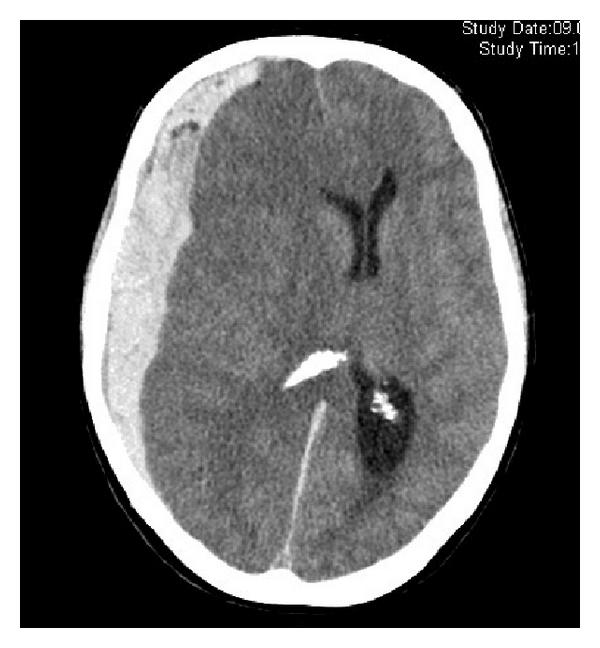

硬腦膜上出血

硬腦膜是腦膜最外層,硬腦膜上出血即腦膜與頭骨之間出血。患者或有「清醒期」,即腦部有出血但人仍清醒、舉止正常,但持續出血並壓迫到腦部組織,就可能突然失去意識。如出血量大,須手術移除血塊。